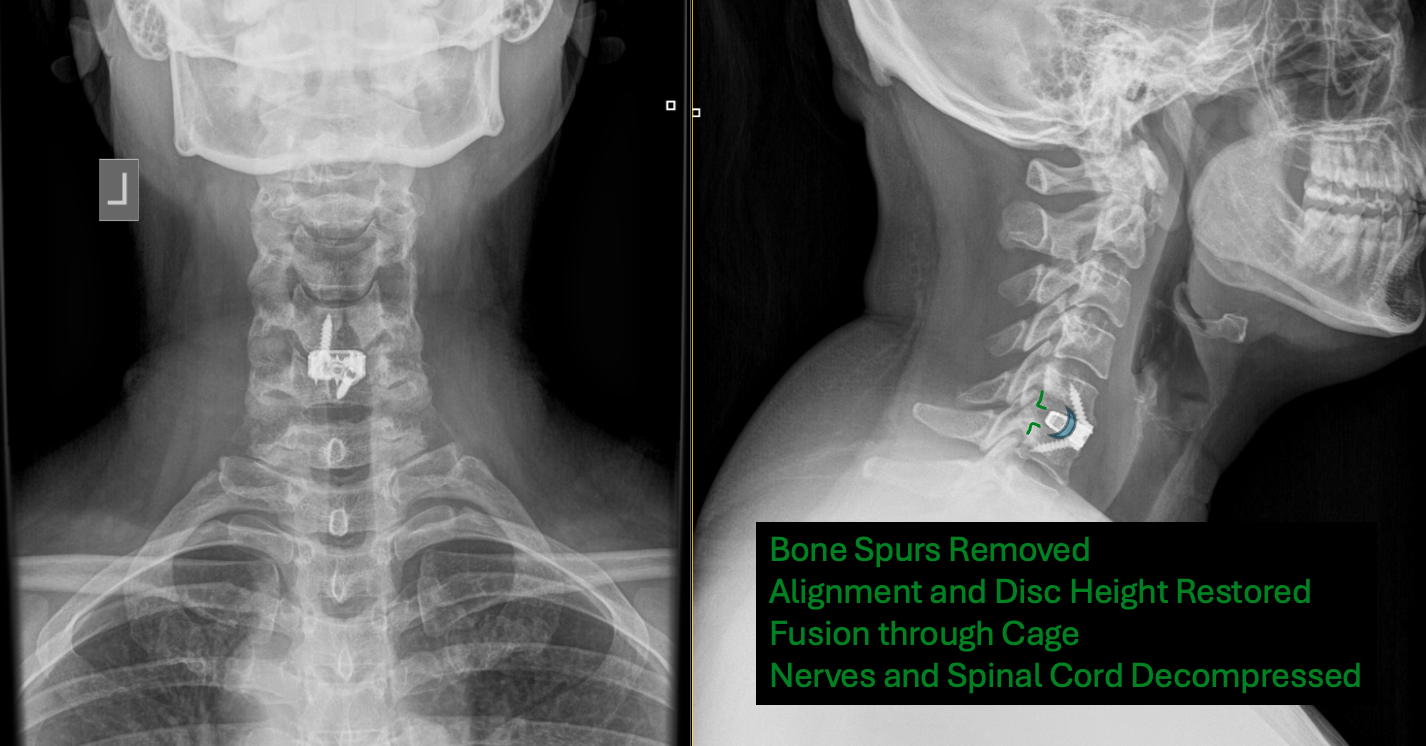

Here is a case example of a patient with bone on bone arthritis, disc collapse and pinched nerve and spinal cord.

Lateral xray demonstrating a collapsed degenerated disc (RED) with bone on bone arthritis and bone spurs compressing nerve roots and the spinal cord. A healthy disc (GREEN) is outlined for comparison.

Xray after surgery demonstrating removal of bone spurs and placement of ACDF fusion cage. The bone spurs have been removed (GREEN), the alignment and disc height have been restored, and the body is forming a fusion or bridge of bone THROUGH the fusion cage (BLUE). This patient experienced immediate, significant relieve of her neck pain and nerve pain symptoms. Individual results may vary. This blog is published for general educational purposes only and is not intended as medical advice.